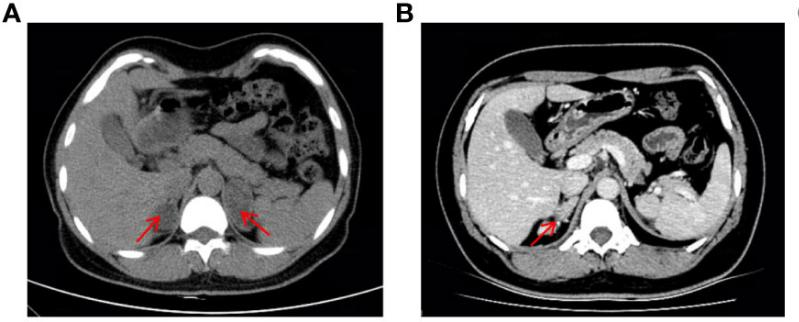

该患者是一名37岁的女性(核型为46,XX),童年时保存生长加速,且婚后一直未有身。2019年因疑诊双侧肾上腺肿瘤入院(图1A),前后举行了两次肾上腺切除术。2022年,患者由于月经不规则被收入内渗透科,CT显示右肾上腺皮质增生复发(图1B),体格检查显示该患者皮肤色素冷静,面部有痤疮和髯毛,泛起男性化体征,生化检查提醒低钾性高血压,高雄血症。均提醒11β-OHD诊断。

图1 患者腹部CT影像